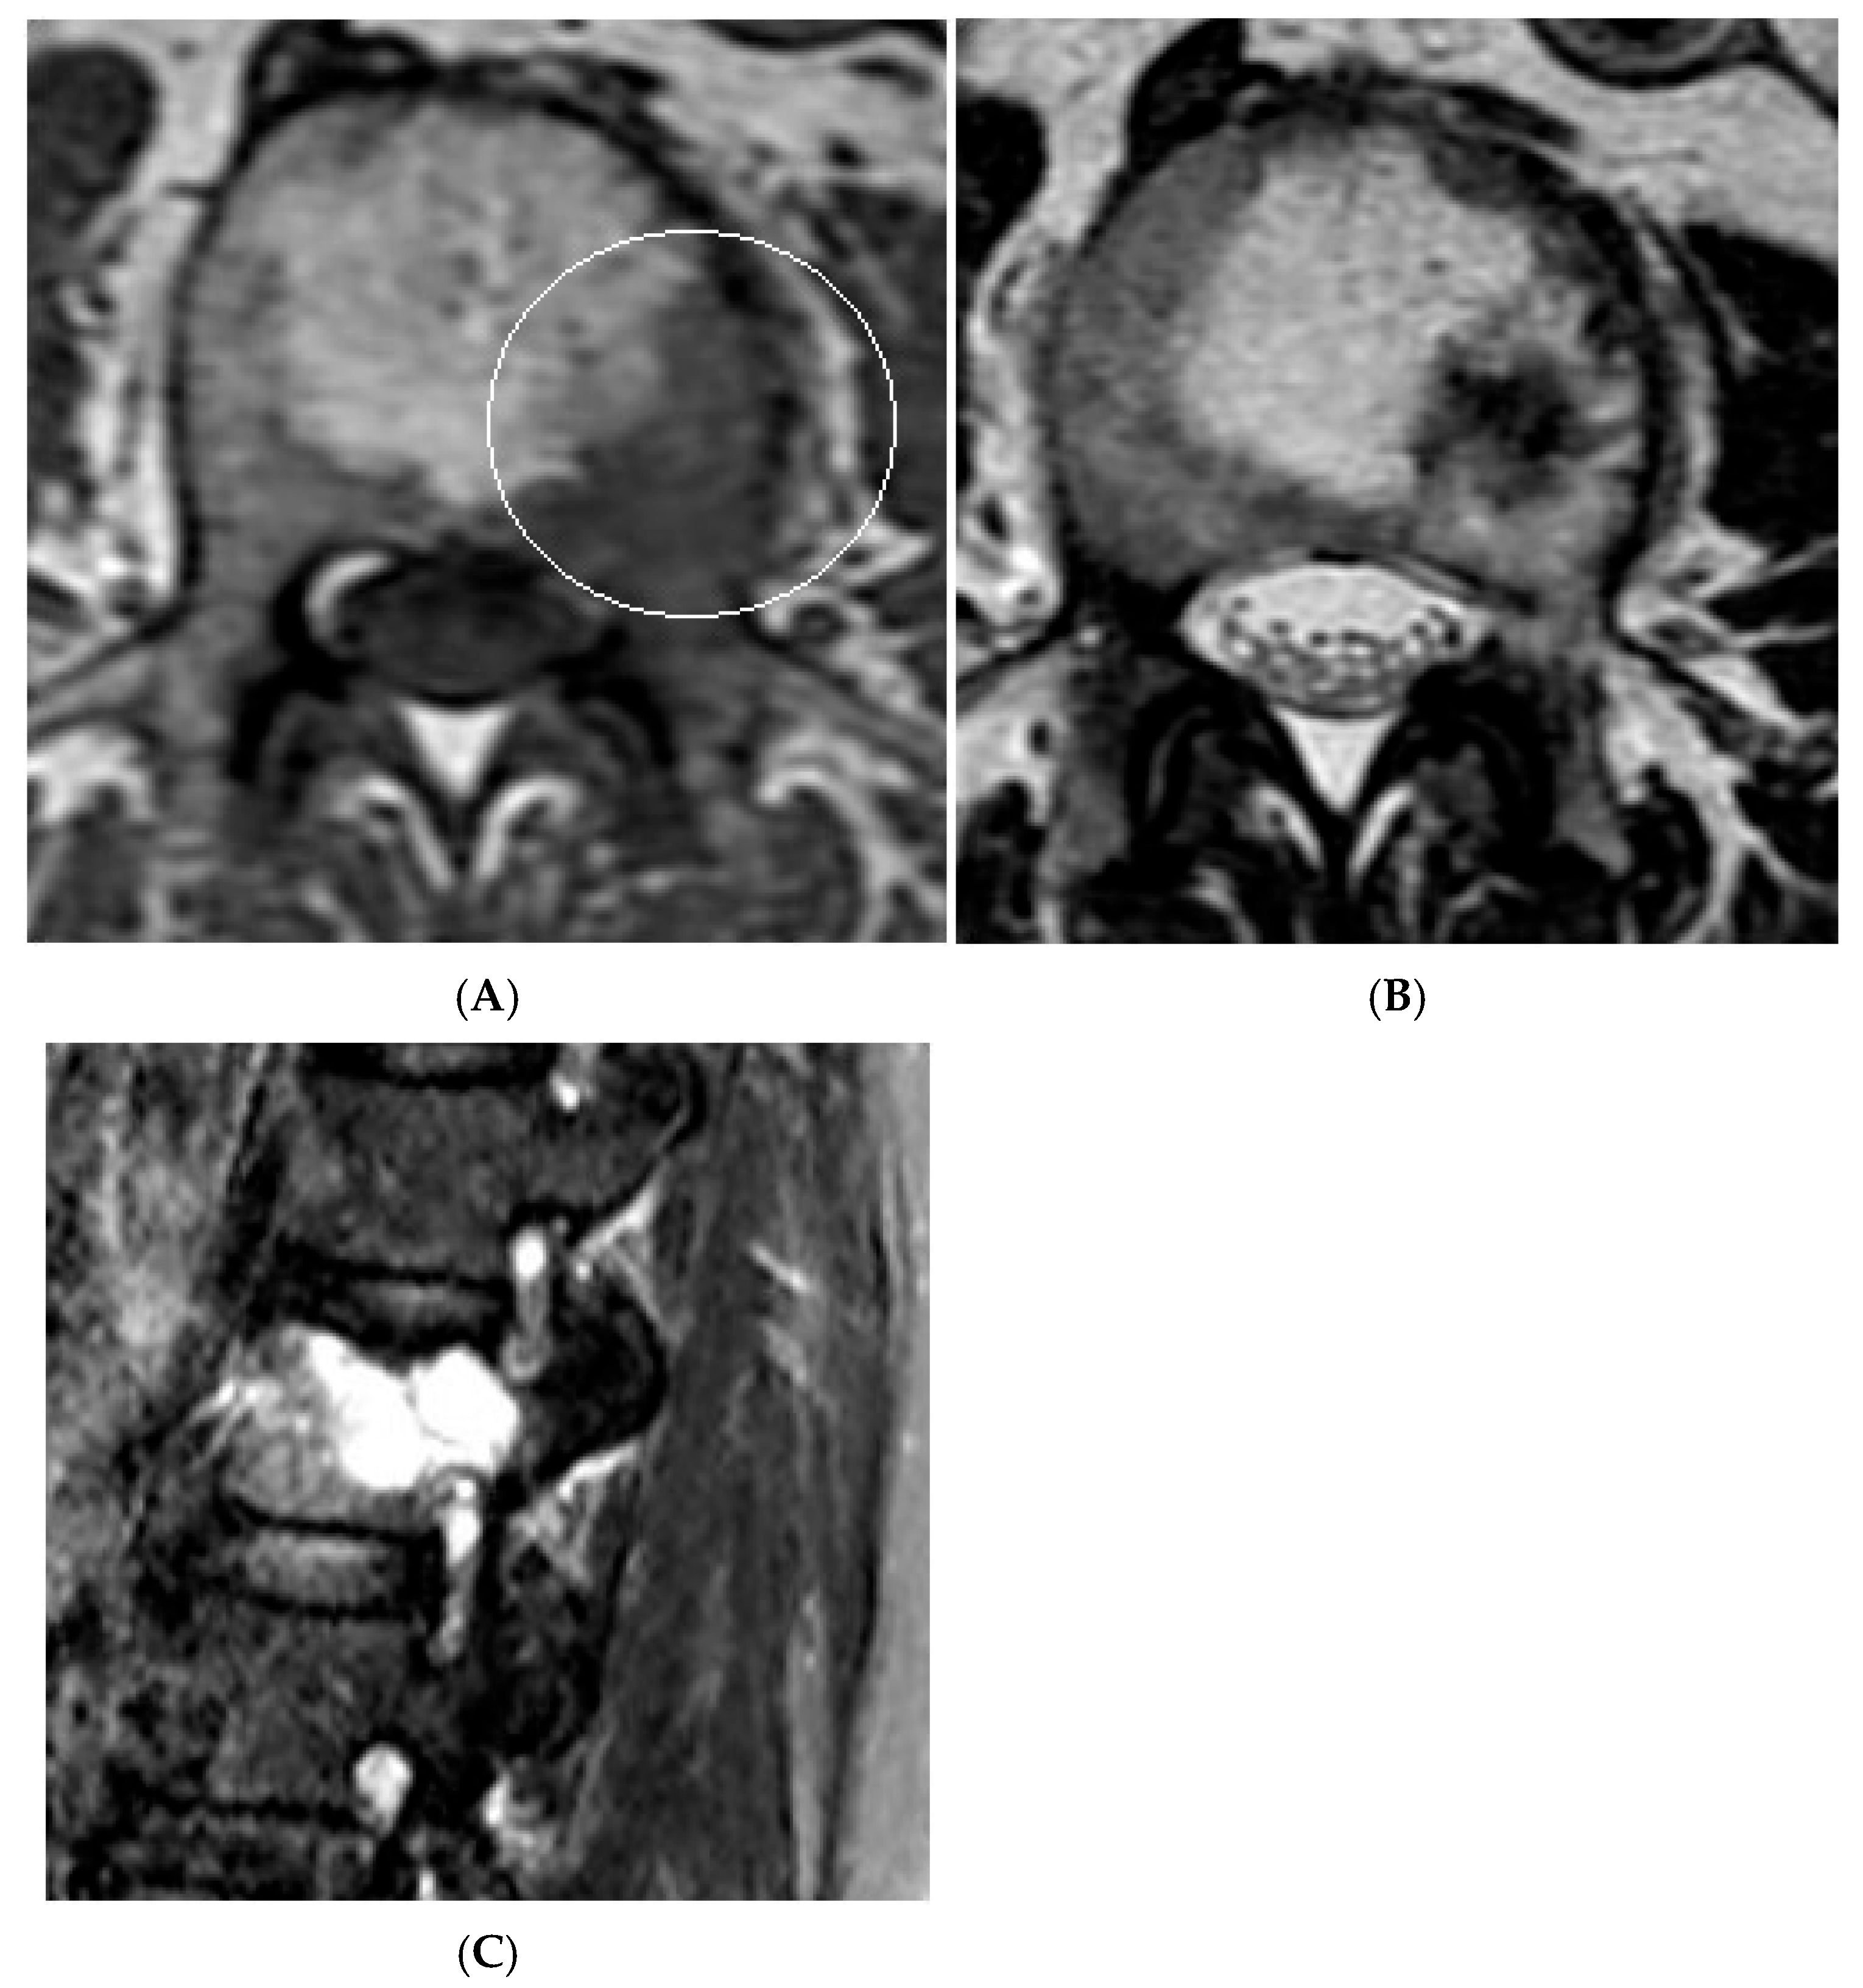

Figure 16.

Collision Lesions—Renal cell carcinoma metastases within a haemangioma of the vertebral body, Case 2. (A) Axial T1W MRI with a typical vertebral body haemangioma with an abnormal low T1 signal in its posterolateral aspect with periosteal change (circled). (B) Axial T2W MRI demonstrates the aggressive lesion within and adjacent to the typical haemangioma in image (A). (C) Sagittal STIR MRI—Fat-suppressed haemangioma with a hyperintense (biopsy-proven) metastases in its posterior aspect involving the pedicle.

Collision lesions of the spine are rare, with few documented cases involving the spinal cord. Notably, metastases from renal cell carcinoma to spinal hemangioblastomas in patients with Von Hippel–Lindau syndrome have been reported [21]. However, collision lesions specifically involving vertebral haemangiomas are exceedingly uncommon, with only a few cases of metastatic infiltration into haemangiomas described in the literature. These include metastases from renal cell carcinoma [22,23], colonic adenocarcinoma [24], and lymphoma [25], each leading to varying clinical manifestations, including spinal cord compression [25] (Figure 14, Figure 15 and Figure 16).